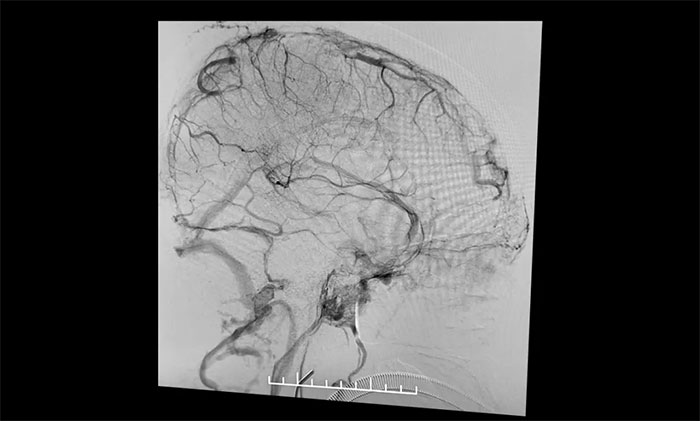

在麻醉科团队及导管室介入团队的密切配合和监护下,4A脑血管病一科主任席刚明教授、4A脑血管病一科副主任王贵平博士小心探索,一边“疏通”,一边不断切换正位及侧位造影,避免造成额外损伤。经过3个多小时的连续奋战,经多次支架取栓、导管抽吸,取出大量暗红色血栓,复查造影见上矢状窦显影明显改善,窦汇、右侧横窦、乙状窦显影改善,左横窦、乙状窦显影可,患者颅内静脉窦顺利再通。行XperCT未见颅内出血。

▲ CT检查发现右侧横窦、窦汇、上矢状窦密度增高